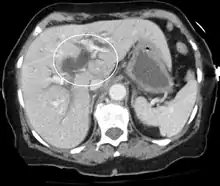

Imaging

Medical imaging such as ultrasound, CT scan, and HIDA scans are useful for detecting bile duct blockage.[32]